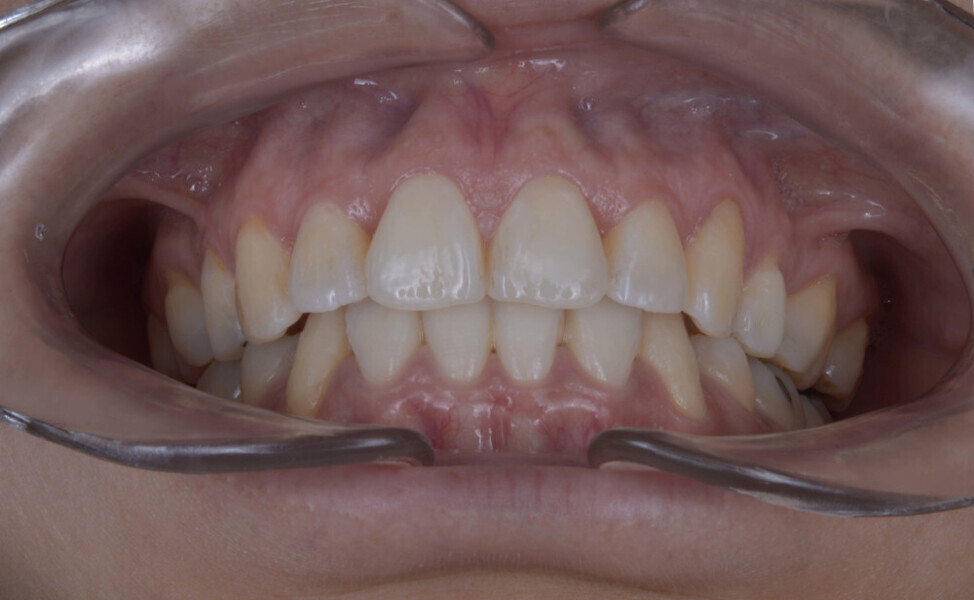

A 35-year-old female patient presented with crowding, muscle and joint pain, and headaches upon awakening. Examination found a skeletal Class I with crowding and bimaxillary protrusion. Facial examination showed a convex profile with protruded lips and a square face shape, intensified on smiling (Figs. 1–4). She reported bruxism, and bilateral masseteric hypertrophy was observed, but there was no alteration of the temporomandibular joints.

Before the aligner treatment began, the maxillary and mandibular second premolars were extracted to create space. With orthodontic treatment, distalisation of the anterior teeth was achieved by employing maximum mandibular anchorage and moderate maxillary anchorage (Figs. 5–7). At the end of the treatment, a stable bilateral Class I occlusion had been achieved, as well as normal inclination and retrusion of the anterior teeth, consequently improving the profile (Figs. 8–10).